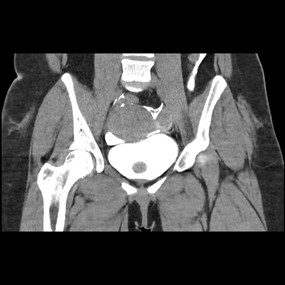

Imaging

- CECT Abdomen with Cystogram

Types of Bladder Injuries

- Extra peritoneal Bladder Injury

- Intraperitoneal Bladder Injury

Extra peritoneal Bladder Injury

Intraperitoneal Bladder Injury

Management

- Conservative management for uncomplicated extraperitonel bladder injuries

- All penetrating or intraperitoneal injuries should be managed by immediate operative repair